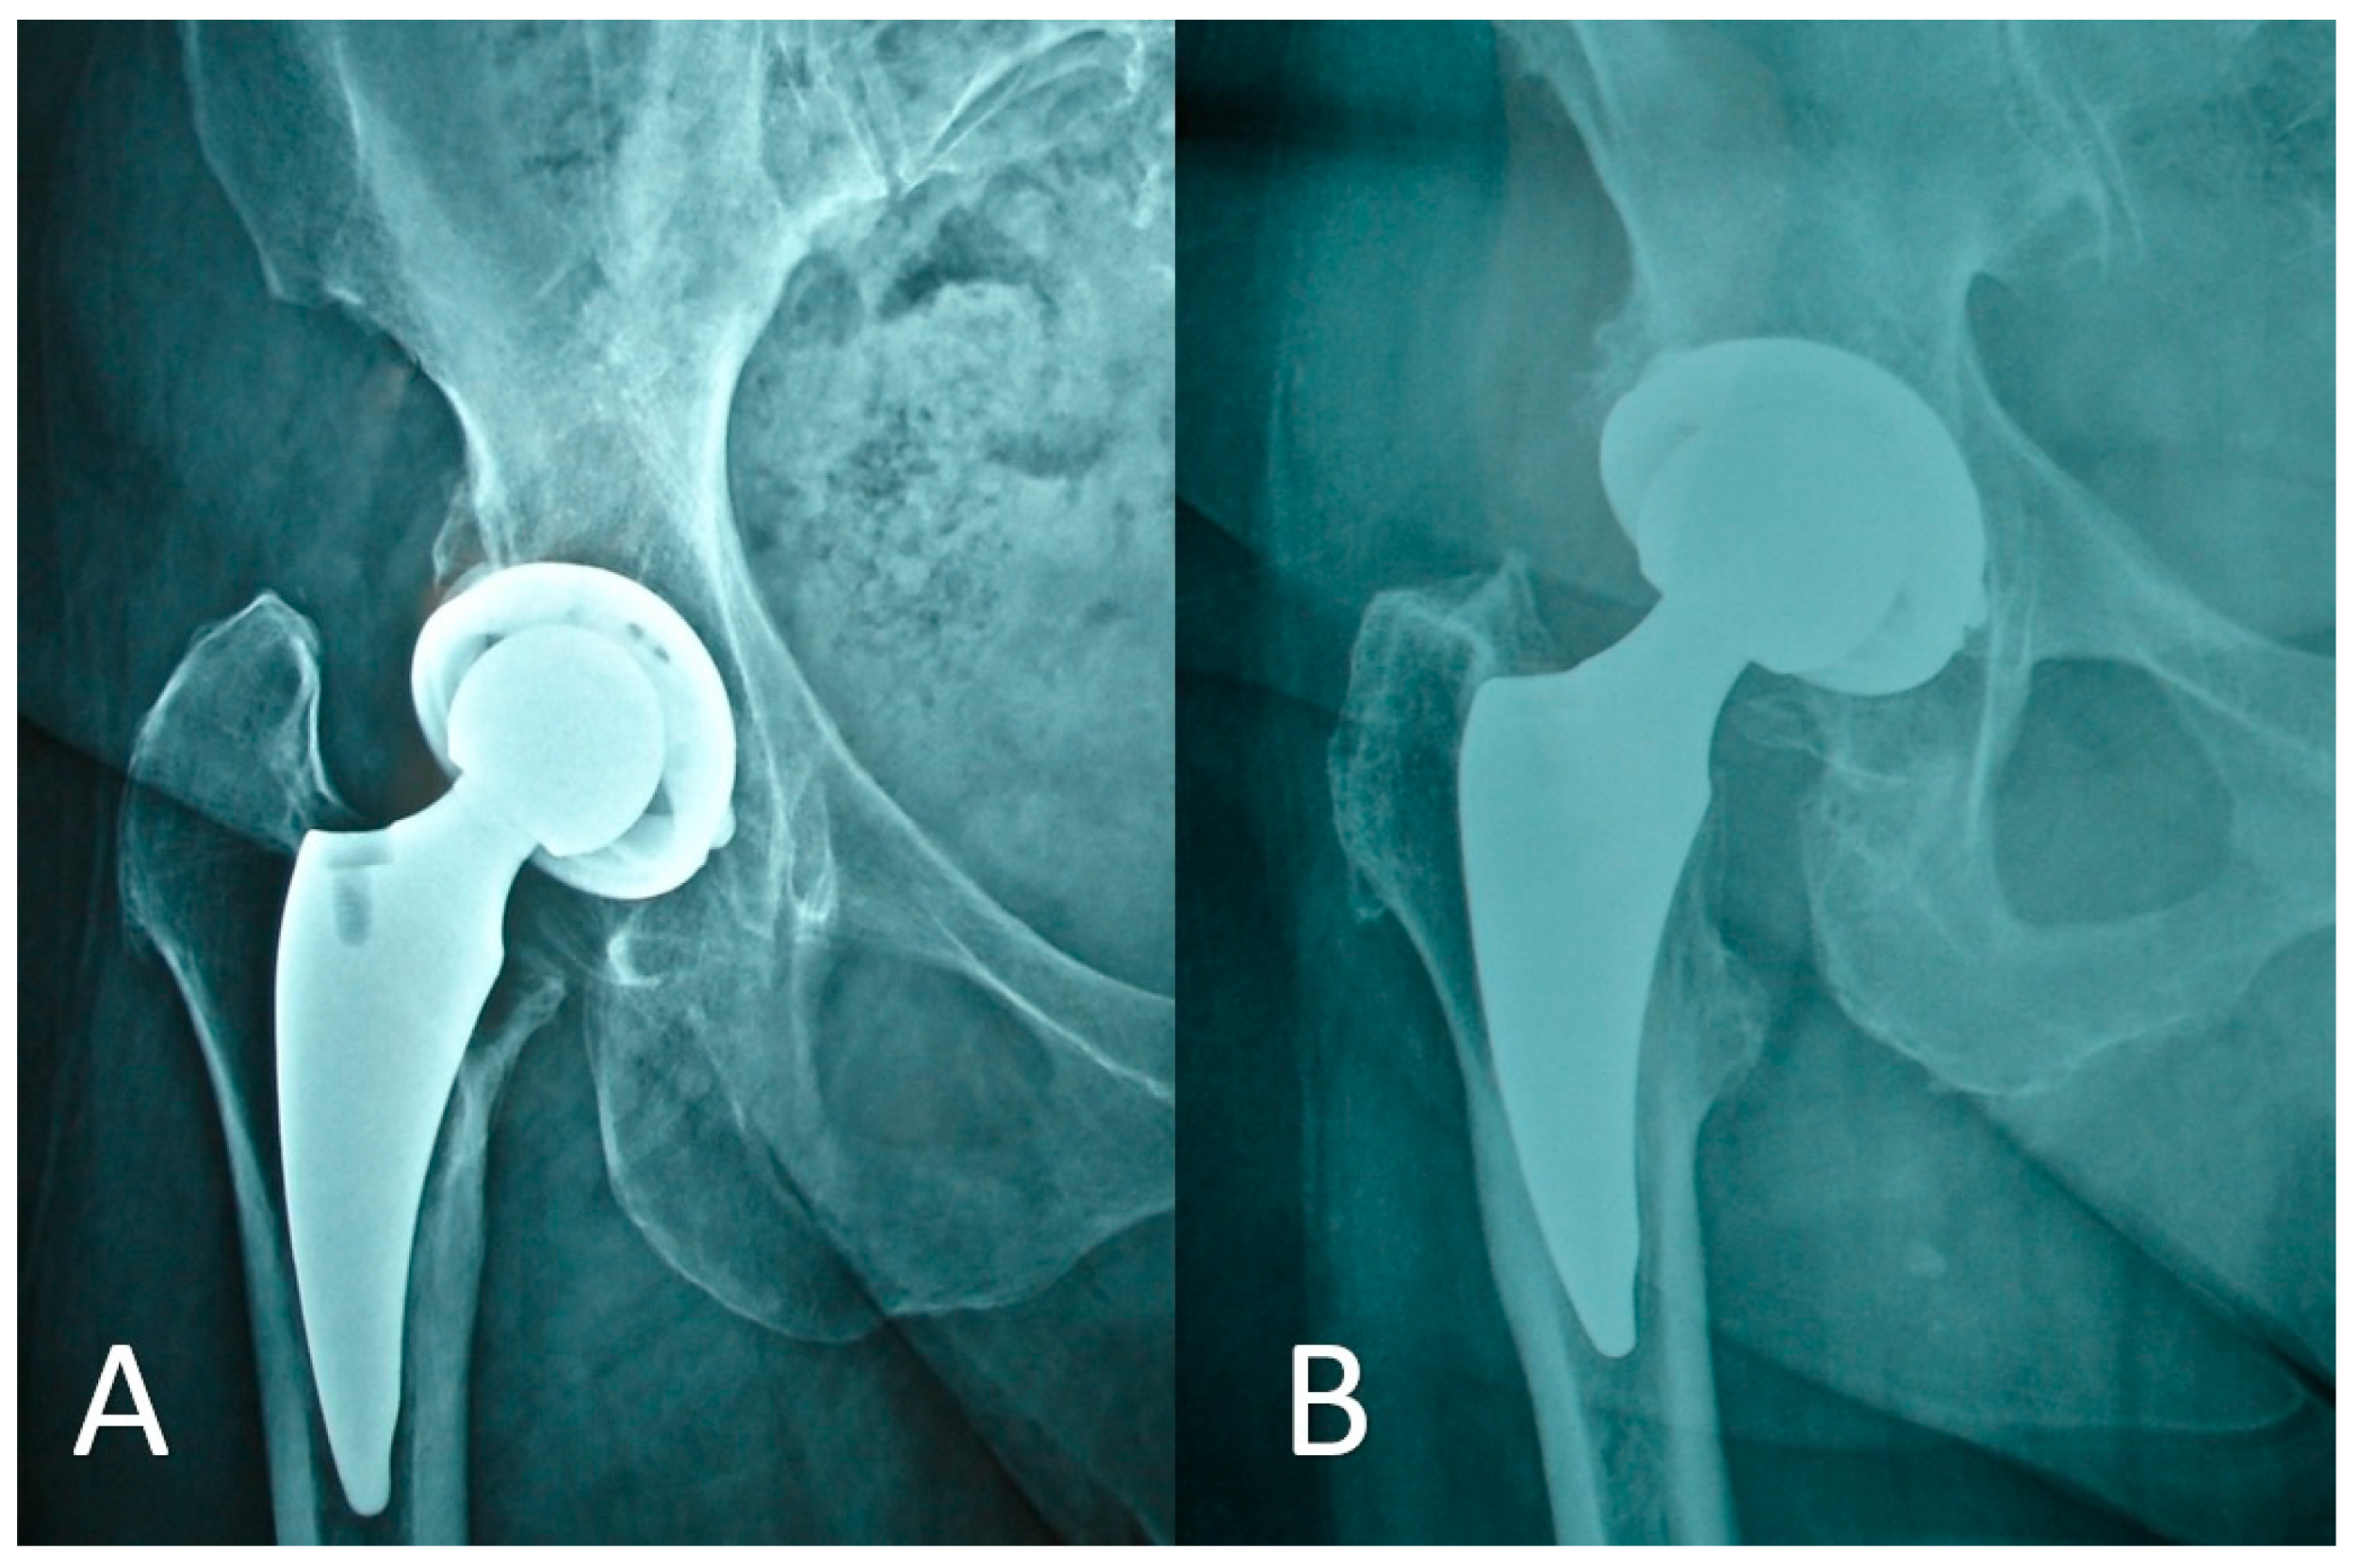

Early Clinical and Radiographic Outcomes of Total Hip Arthroplasty with DELTA ST-C Cup and MINIMA S Stem

2. Methods

3. Results